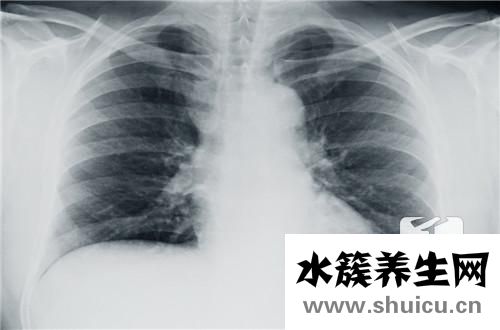

胸膜炎是任何人都可能發(fā)生的常見疾病。 一些患者總是認(rèn)為該病并不嚴(yán)重,不需要太多的治療。 事實(shí)證明,這個(gè)想法是極端錯(cuò)誤的。 如果治療不及時(shí),可能會發(fā)生許多后遺癥,例如胸腔積液,肉芽組織增生和肺功...